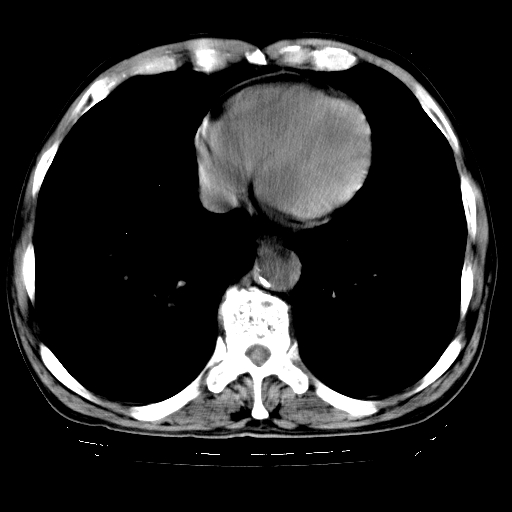

以下是引用hhcckk在2009-1-1 15:38:00的发言:[br]左下肺少许絮状模糊影--考虑感染[br]两肺散在小点状密度增高影--结合病史考虑矽肺?[br]气管壁钙化--可能由于老年退变性引起的